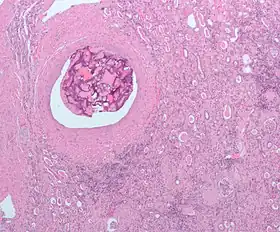

Micrograph of embolic material in the artery of a kidney. The kidney was surgically removed because of cancer. H&E stain.